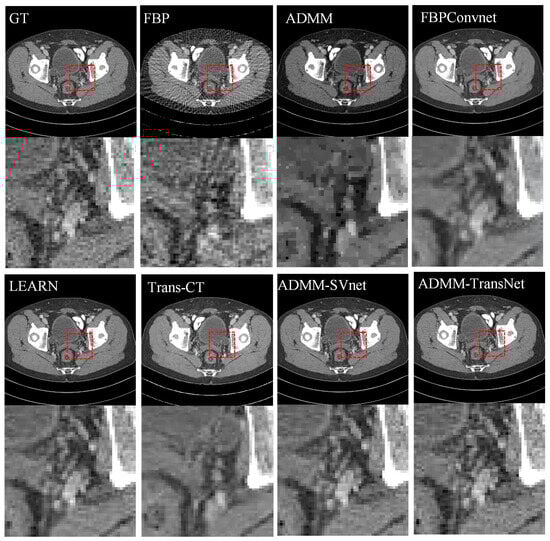

4.1. Simulation Data Research

| Views | 128 | 64 | 32 | ||||||

|---|---|---|---|---|---|---|---|---|---|

| Metric | PSNR | SSIM | MAE | PSNR | SSIM | MAE | PSNR | SSIM | MAE |

| FBP | 26.140 | 0.808 | 0.044 | 22.067 | 0.612 | 0.074 | 18.935 | 0.539 | 0.126 |

| ADMM | 33.751 | 0.929 | 0.021 | 30.883 | 0.915 | 0.027 | 29.753 | 0.907 | 0.038 |

| FBPConvNet | 39.854 | 0.952 | 0.020 | 34.243 | 0.938 | 0.028 | 30.648 | 0.916 | 0.035 |

| LEARN | 42.972 | 0.975 | 0.009 | 39.943 | 0.977 | 0.012 | 36.935 | 0.938 | 0.019 |

| Trans-CT | 40.877 | 0.966 | 0.011 | 35.855 | 0.941 | 0.019 | 32.430 | 0.922 | 0.023 |

| ADMM-SVnet | 43.229 | 0.995 | 0.007 | 42.974 | 0.989 | 0.008 | 40.212 | 0.972 | 0.013 |

| Ours | 44.633 | 0.996 | 0.006 | 43.726 | 0.992 | 0.007 | 42.036 | 0.979 | 0.011 |